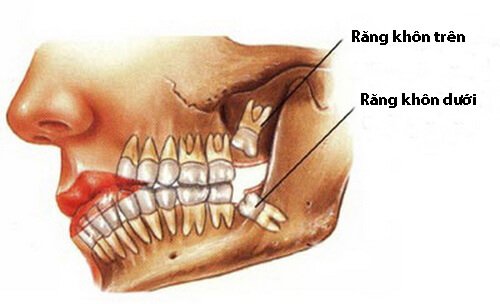

Nhổ răng khôn gây hại có nhiều lợi ích to lớn, không chỉ cho hàm răng mà còn cho sức khỏe tổng thể. Tuy nhiên, tất cả các điều trị y khoa luôn có lợi ích và biến chứng song hành. Hiểu về biến chứng sau khi nhổ răng khôn cũng quan trọng như khi chúng ta tìm hiểu về lợi ích vậy.

Nhổ răng khôn là một phẫu thuật trong miệng. Vì vậy có thể có những biến chứng về phẫu thuật đặc thù, cũng như những biến chứng riêng biệt khác như sau:

5. Gây tổn thương tới các dây thần kinh

Nhổ răng khôn có thể khiến tổn thương dây thần kinh ống răng, dây lưỡi. Khiến bạn bị tê, nóng rát hoặc mất cảm giác ở môi, lưỡi, vùng xương hàm dưới tạm thời, nhưng cũng có trường hợp là vĩnh viễn. Đặc biệt càng lớn tuổi, sự bồi đắp cement chân răng theo tuổi làm chân răng dài ra và nằm sát ống thần kinh hơn. Sự tổn thương tới các dây thần kinh càng có nguy cơ nghiêm trọng hơn.

Với biến chứng này, để dự phòng và xử lý, tại các nha khoa uy tín, khách hàng sẽ được chụp phim kiểm tra kỹ vị trí chân răng và vị trí ống thần kinh răng dưới. Từ đó dự trù được các trường hợp xảy ra. Điều chỉnh phẫu thuật đảm bảo an toàn và phù hợp nhất với khách hàng.

6. Thủng xoang hàm

Thủng xoang hàm là một biến chứng sau khi nhổ răng khôn hàm trên. Vì xoang hàm trên đôi khi nằm gần các chân răng hàm trên, tác động nhổ thô bảo, không đúng kỹ thuật có thể đẩy chân răng vào xoang.